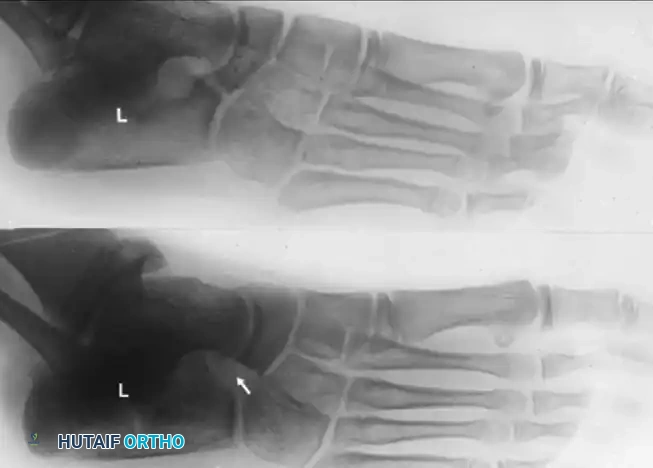

Thorough radiographic evaluation is mandatory before proceeding with a calcaneonavicular bar resection. Standard weight-bearing anteroposterior, lateral, and oblique radiographs of the foot should be obtained. The 45-degree internal oblique view is the gold standard for visualizing a calcaneonavicular bar, which will appear as a solid bony bridge or an irregular, sclerotic pseudoarticulation between the anterior process of the calcaneus and the navicular.

- Verification of Resection: We strongly recommend a lateral oblique radiographic examination on the operating table after resection to confirm adequate removal. Usually, a 1.5- to 2.5-cm segment of the bar must be removed. Ensure that the lateral fourth of the articular surface of the talus is left uncovered by the navicular; this serves as an anatomic landmark confirming adequate excision.